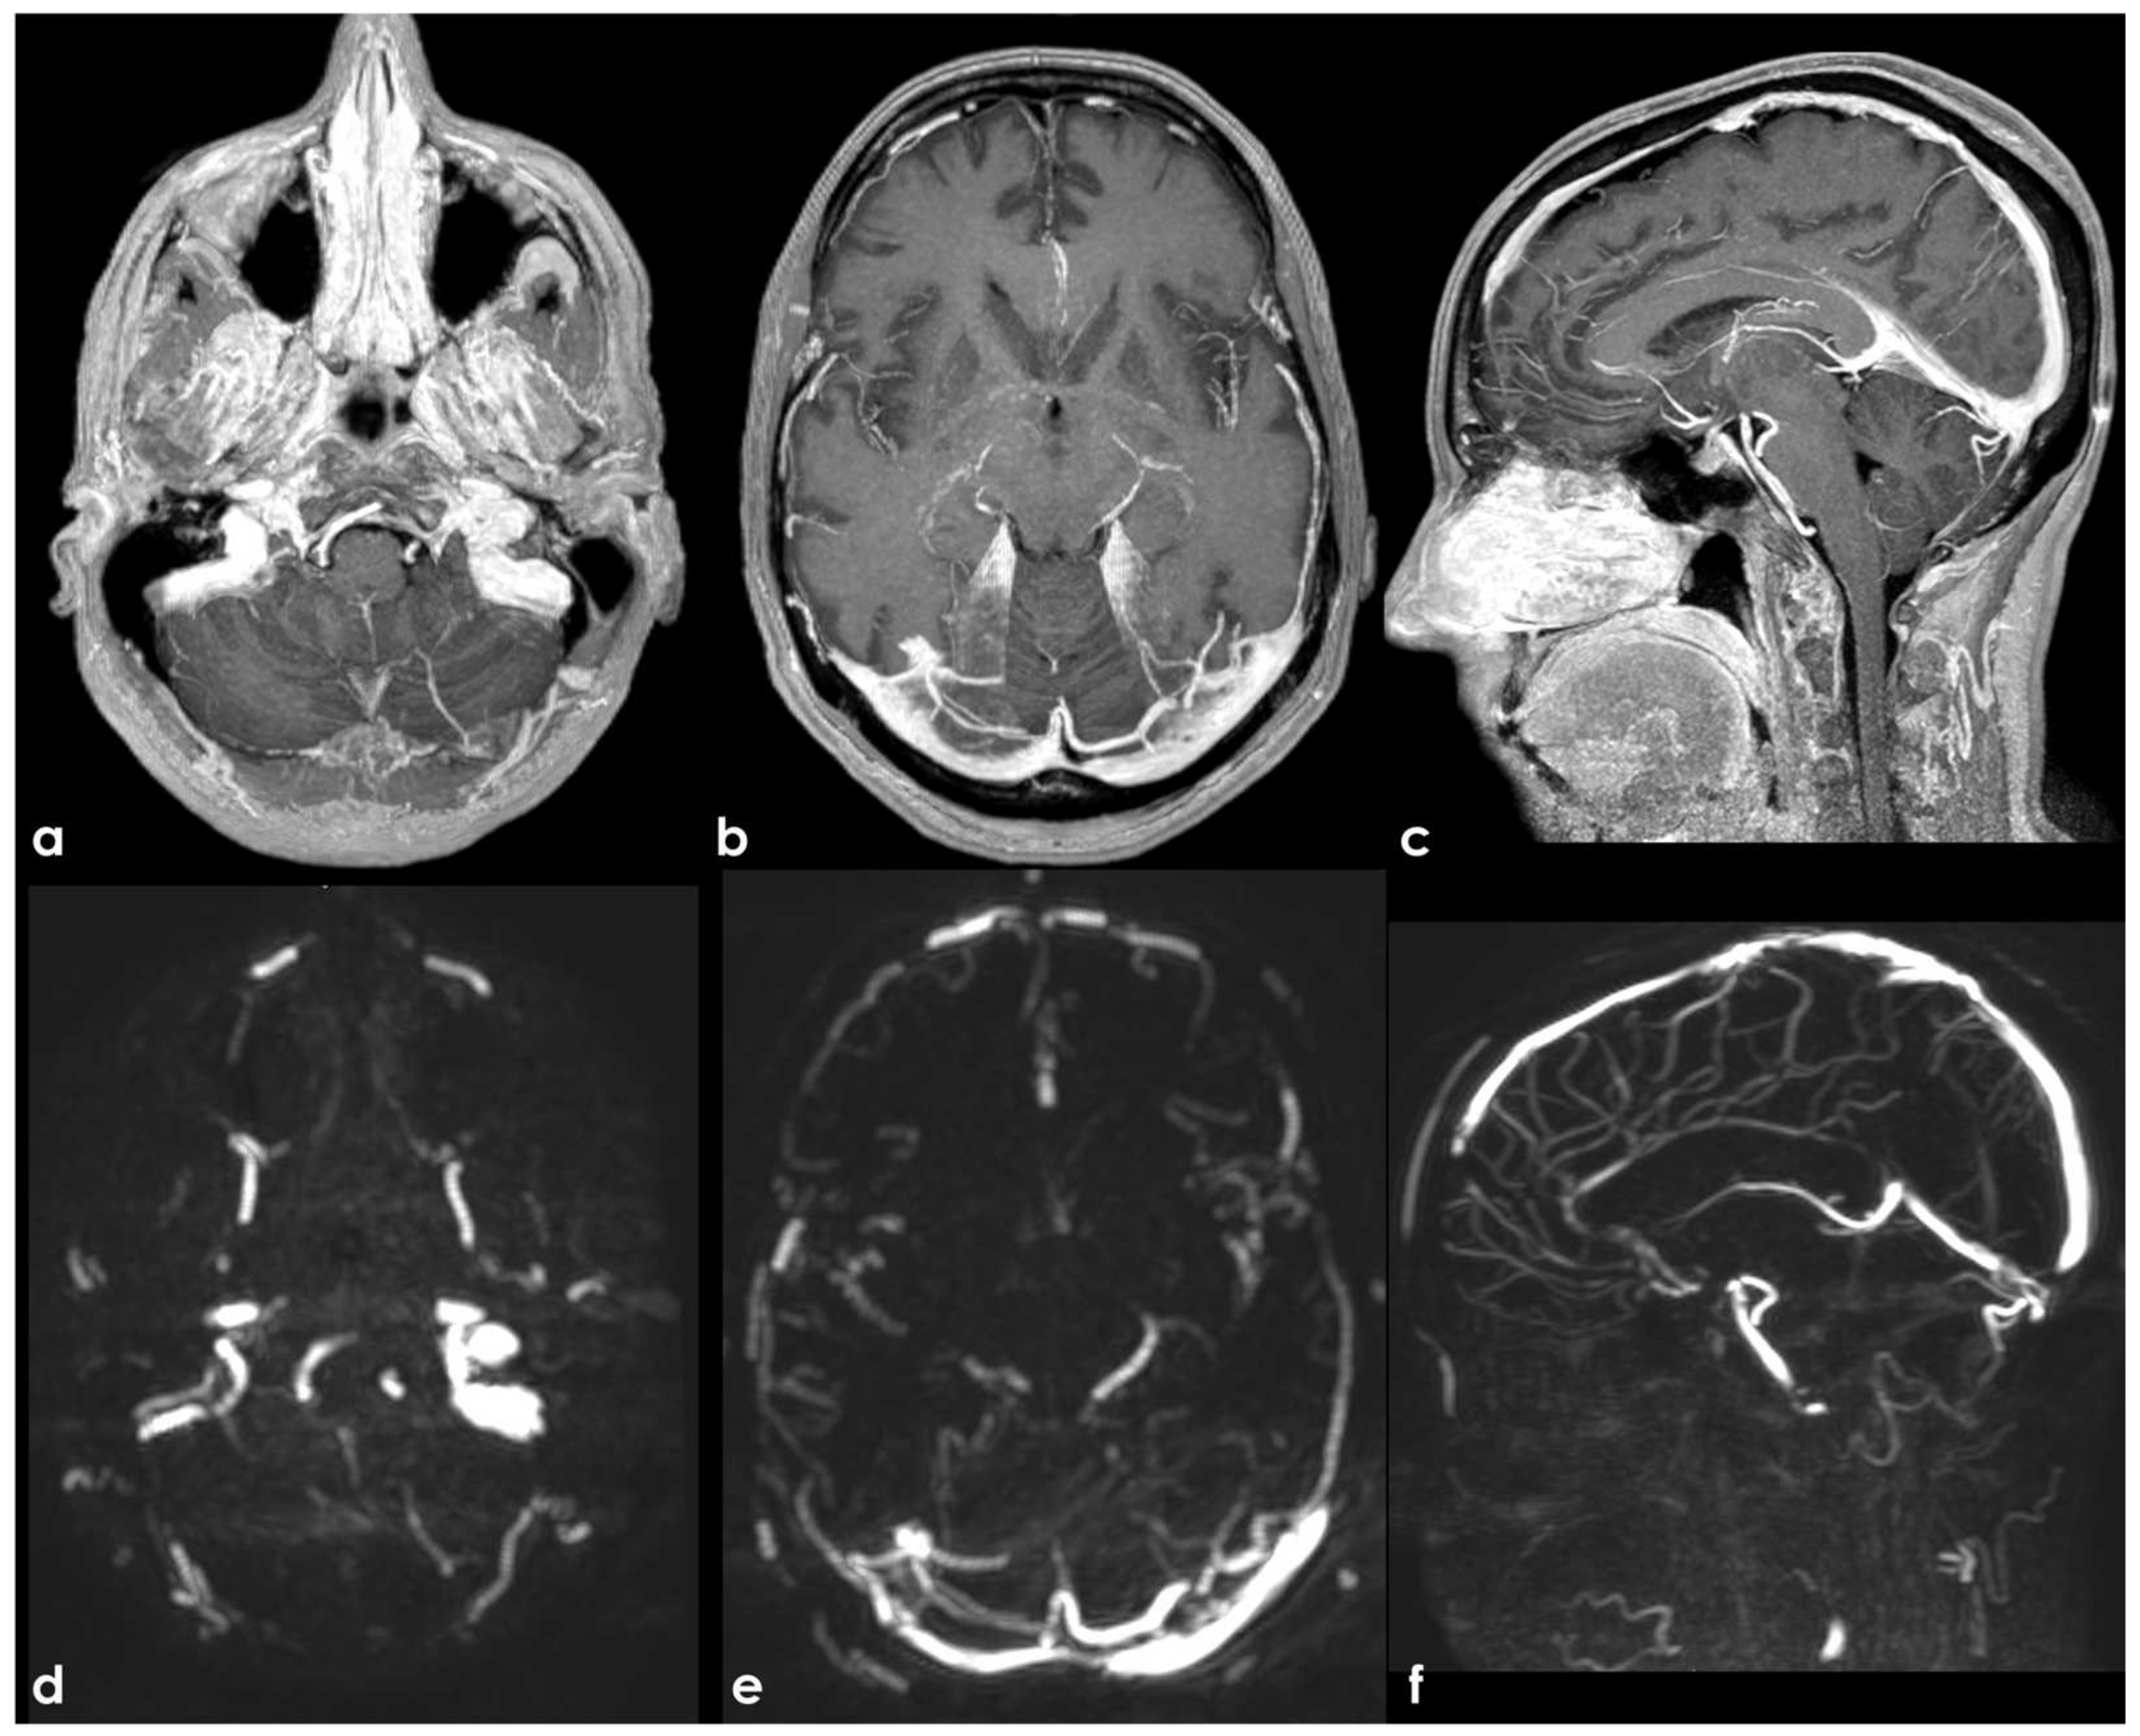

4.1.2. Arachnoid Granulations

- Leach, J.L.; Jones, B.V.; Tomsick, T.A.; Stewart, C.A.; Balko, M.G. Normal appearance of arachnoid granulations on contrast-enhanced CT and MR of the brain: Differentiation from dural sinus disease. AJNR Am. J. Neuroradiol. 1996, 17, 1523–1532. [Google Scholar]

- Roche, J.; Warner, D. Arachnoid granulations in the transverse and sigmoid sinuses: CT, MR, and MR angiographic appearance of a normal anatomic variation. AJNR Am. J. Neuroradiol. 1996, 17, 677–683. [Google Scholar]

- Leach, J.; Meyer, K.; Jones, B.; Tomsick, T. Large arachnoid granulations involving the dorsal superior sagittal sinus: Findings on MR imaging and MR venography. Am. J. Neuroradiol. 2008, 29, 1335–1339. [Google Scholar] [CrossRef]

- VandeVyver, V.; Lemmerling, M.; De Foer, B.; Casselman, J.; Verstraete, K. Arachnoid granulations of the posterior temporal bone wall: Imaging ap-pearance and differential diagnosis. AJNR Am. J. Neuroradiol. 2007, 28, 610–612. [Google Scholar] [PubMed]

- Haroun, A.; Mahafza, W.; Al Najar, M. Arachnoid granulations in the cerebral dural sinuses as demonstrated by con-trast-enhanced 3D magnetic resonance venography. Surg. Radiol. Anat. 2007, 29, 323–328. [Google Scholar] [CrossRef]